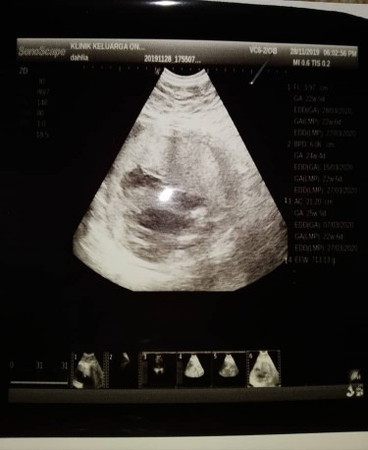

Scan 23w

Salam... Korg phm tk tgk scan ni... Cube teka lelaki ke pmpuan?? ?

Sy rse boy..nmpk mcm ade bebird tp kabur

Mcm girk

Its a boy π¦